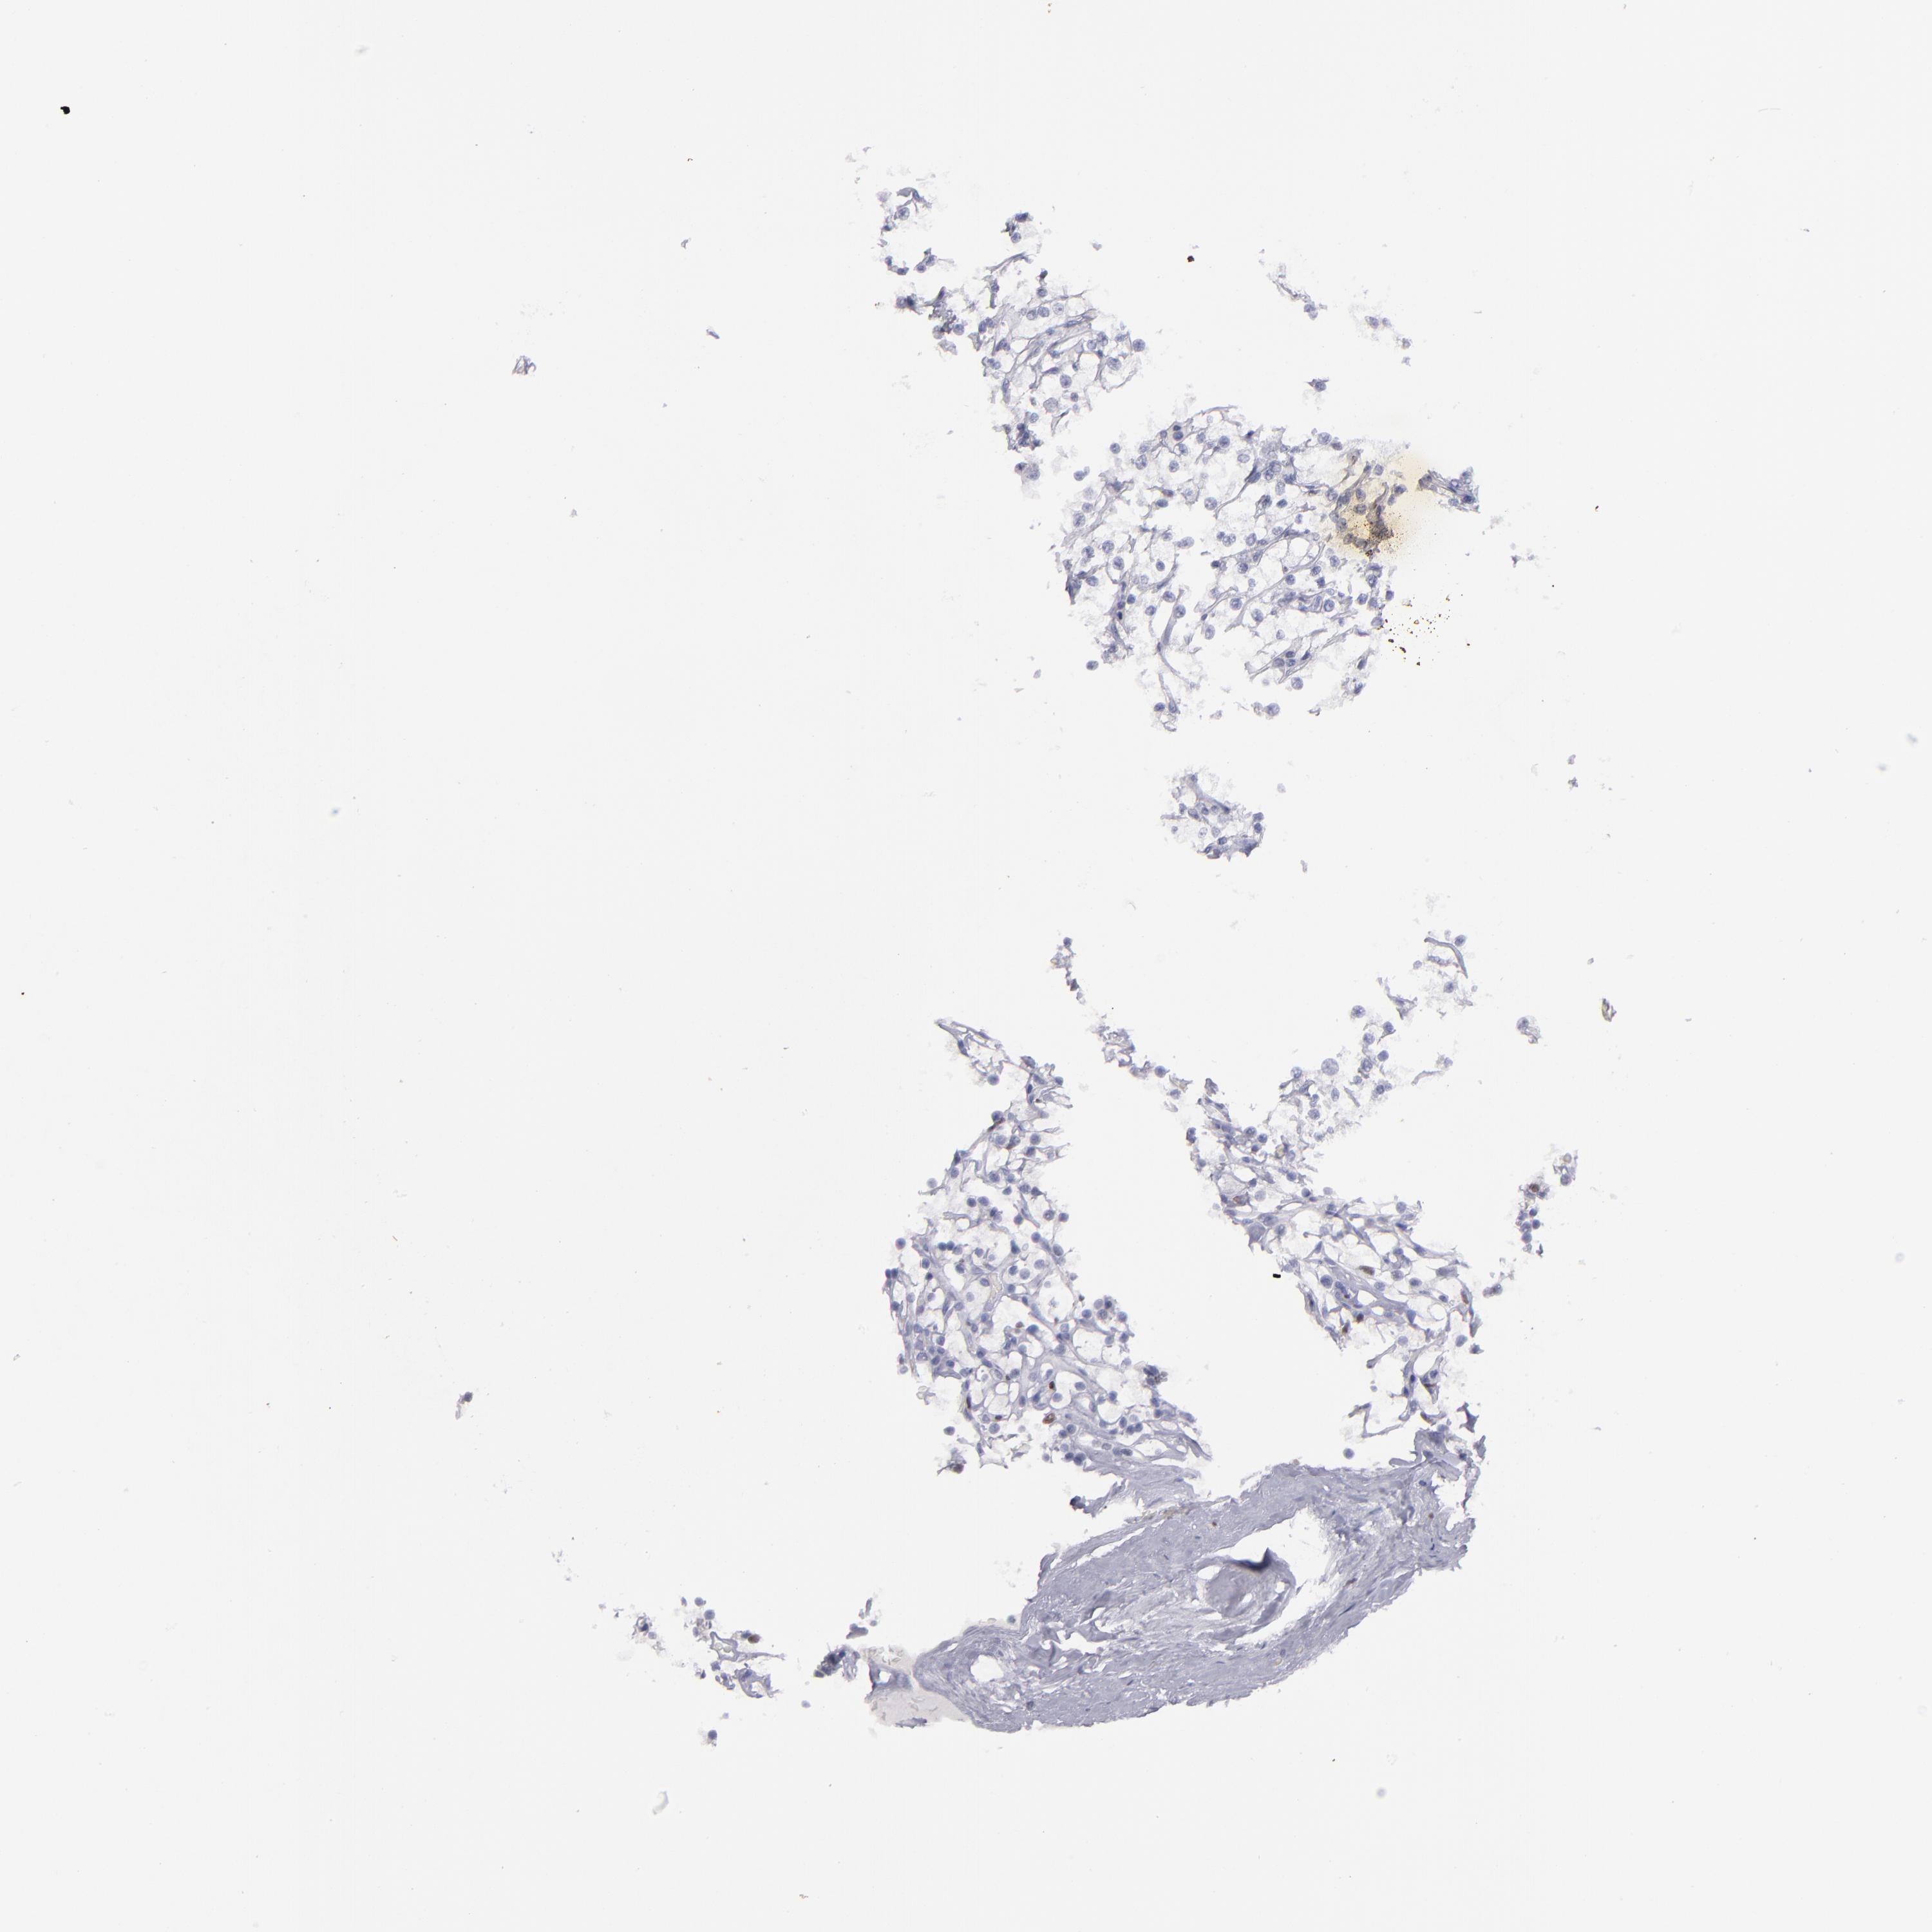

KIDNEY RENAL PAPILLARY CELL CARCINOMA (TCGA) - Interactive survival scatter ploti

The Survival Scatter plot shows the clinical status (i.e. dead or alive) for all individuals in the patient cohort, based on the same data that underlies the corresponding Kaplan-Meier plots. Patients that are alive at last time for follow-up are shown in blue and patients who have died during the study are shown in red.

The x-axis shows the expression levels (FPKM) of the investigated gene in the tumor tissue at the time of diagnosis. The y-axis shows the follow-up time after diagnosis (years). Both axes are complimented with kernel density curves demonstrating the data density over the axes. The top density plot shows the expression levels (FPKM) distribution among dead (red) and alive patients (blue). The right density plot shows the data density of the survived years of dead patients with high and low expression levels respectively, stratified using the cutoff indicated by the vertical dashed line through the Survival Scatter plot. This cutoff is automatically defined based on the FPKM cutoff that minimizes the p-score. The cutoff can be changed by dragging the vertical line or by entering a cutoff value in the square labeled "Current cut-off".

Under the Survival Scatter plot the p-score landscape (black curve; left axis) is shown together with dead median separation (red curve; right axis). Dead median separation is the difference in median mRNA expression between patients who have died with high and low expression, respectively. It is calculated as follows: median FPKM expression of dead patients with high expression - median FPKM expression of dead patients with low expression. This is intended to aid the user in visually exploring custom cutoffs and the associated p-scores and dead median separation.

Individual patient data is displayed and can be filtered by clicking on one or more of the category buttons on the top of the page. Categories describing expression level and patient information include: high, low, alive, dead, female, male and tumor stages. The scale of the x-axis can be toggled between linear and log-scale by clicking on the "x log" button. Mouse-over function shows TCGA ID, patient information and mRNA expression (FPKM) for each patient.

& Survival analysisi

Kaplan-Meier plots summarize results from analysis of correlation between mRNA expression level and patient survival. Patients were divided based on level of expression into one of the two groups "low" (under cut off) or "high" (over cut off). X-axis shows time for survival (years) and y-axis shows the probability of survival, where 1.0 corresponds to 100 percent.

IRF8 is not prognostic in Kidney Renal Papillary Cell Carcinoma (TCGA)